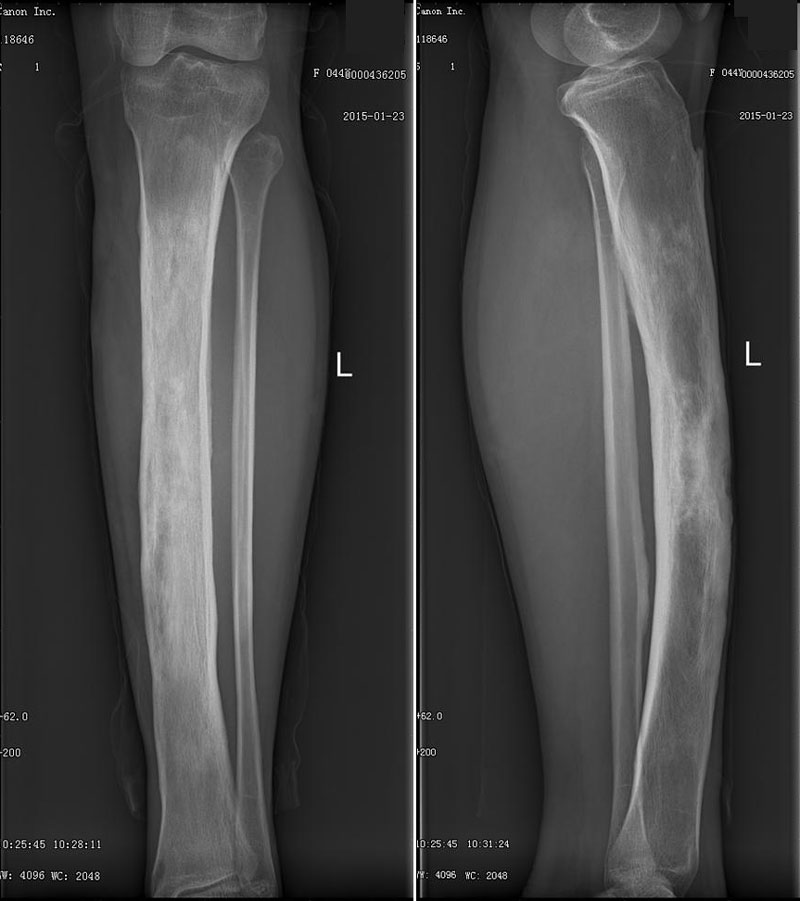

CL2952:胫骨慢性骨髓炎

女性,44岁。 主诉:左小腿胫骨骨髓炎35年,渗液不适1年余。 现病史:患者自述35年前无明显诱因出现左小腿胫骨上段环形肿物,局部皮肤潮红,当时疼痛剧烈,不能行走,并有渗液,在当地医院住院治疗,诊断为骨髓炎, ...